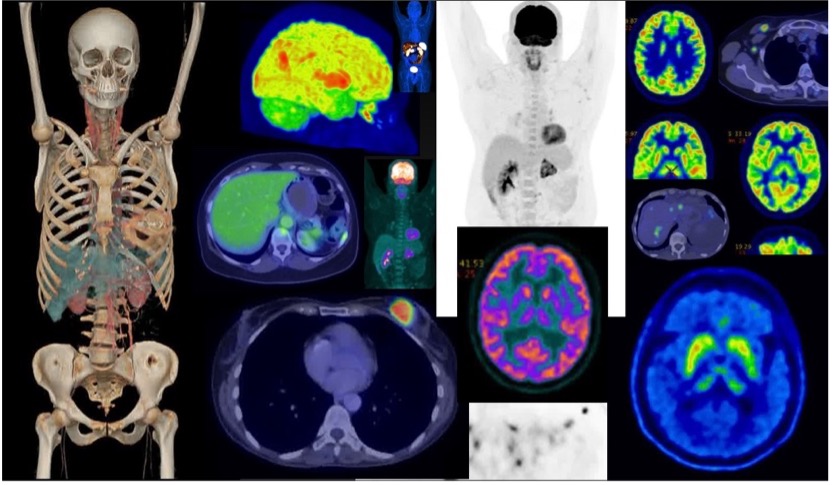

![PET/CT images of [18F]FEAU accumulation in the anterior... | Download ...](https://www.researchgate.net/profile/Frank-Marini/publication/51632738/figure/fig4/AS:213402938023945@1427890633931/PET-CT-images-of-18FFEAU-accumulation-in-the-anterior-interventricular-lymphatic-trunk.png)